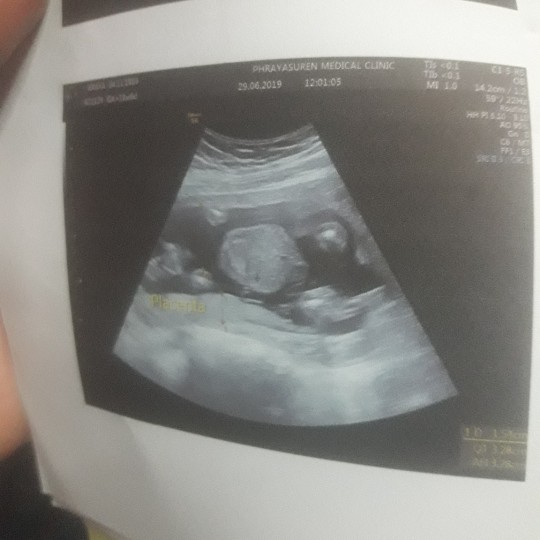

ช่วยดูทีค่ะชายหรือหญิง